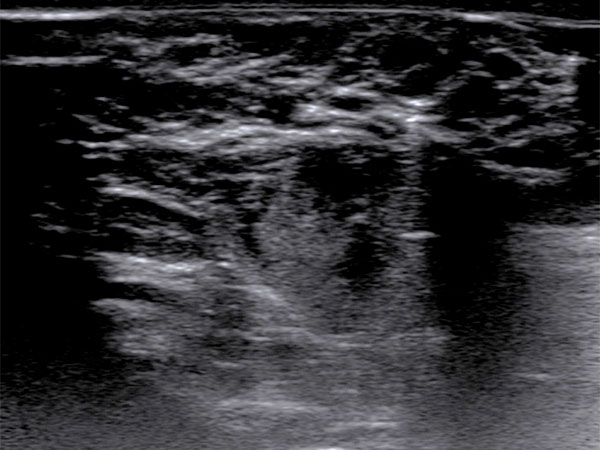

Es wird zur endgültigen Diagnosesicherung jetzt noch eine sonogesteuerte Stanzbiopsie mit einer 16-Gauge-Einmalbiopsiepistole aus der Läsion am Labium majus rechts entnommen. Die in die Läsion vorgeschobene Biopsienadel erzeugt eine starke distale Schallauslöschung im B-Bild-Ultraschall.